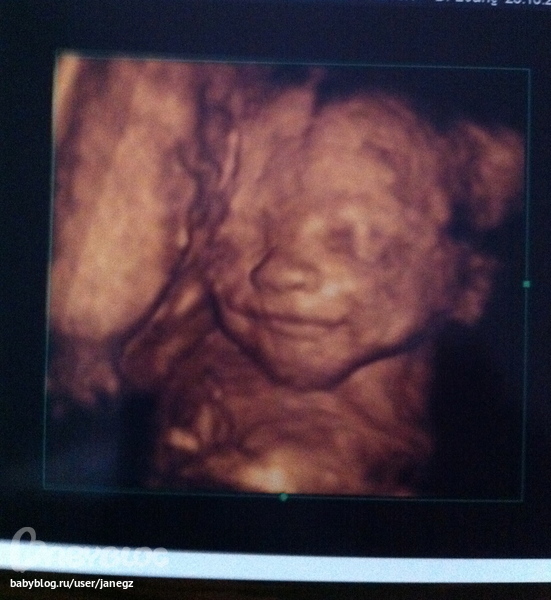

Внешность и красотаУлыбается)

девочки.показывайте своих крох) желательно с "оригиналом"))